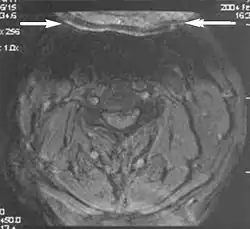

Wrap-around

A wrap-around artifact also known as an aliasing artifact, is a result of mismapping of anatomy that lies outside the field of view but within the slice volume.[4] The selected field of view is smaller than the size of the imaged object. The anatomy is usually displaced to the opposite side of the image (Figs 6 and 7). It can be caused by non-linear gradients or by undersampling of the frequencies contained within the return signal.[1] The sampling rate must be twice the maximal frequency that occurs in the object (Nyquist sampling limit). If not, the Fourier transform will assign very low values to the frequency signals greater than the Nyquist limit. These frequencies will then ‘wrap around’ to the opposite side of the image, masquerading as low-frequency signals. In the frequency encode direction a filter can be applied to the acquired signal to eliminate frequencies greater than the Nyquist frequency. In the phase encode direction, artifacts can be reduced by an increasing number of phase encode steps (increased image time). For correction, a larger field of view may be chosen.[1]